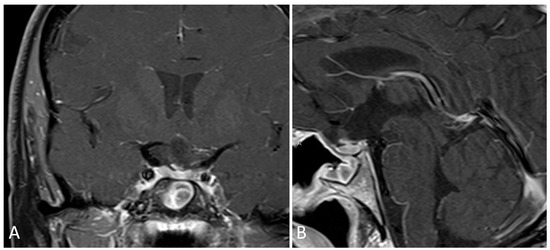

3.1.2. Illustrative Case

3.1.4. Illustrative Case